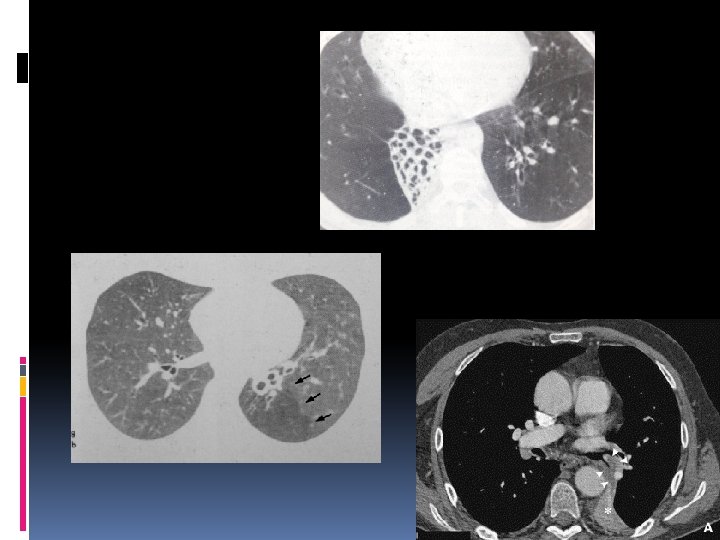

Signes radiologiques opacité mixte pleuro-pulmonaire ovalaire ou arrondie au contact de la plèvre pariétale, ou reliée à elle par une opacité linéaire Attraction de la scissure épaississement pleural en regard ou épanchement les pyramides basales ++ déplacement arciforme des structures vasculaires et bronchiques convergent vers un pôle de l'opacité, réalisant une image en « queue de comète »

en TDM Triade classique : masse sous pleurale ronde Signes pleureux en contact Encorbellement des vaisseaux et bronches autour de la masse.

Les atélectasies en bande Sur la radiographie opacités linéaires relativement épaisses ne franchissent pas les scissures trajet est horizontal extrémité distale au contact de la plèvre pyramide basale++